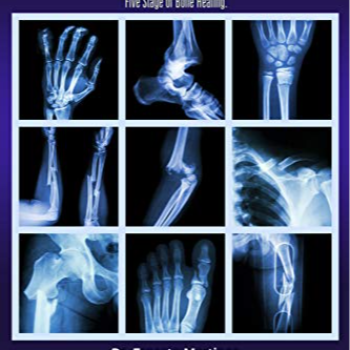

The treatment process begins with thorough diagnostic imaging, including X-rays and CT scans, to accurately assess the type and extent of the fracture. Based on the diagnosis, a personalized treatment plan is developed. This may include non-surgical methods such as casting or splinting to stabilize the bone and promote natural healing. For more complex fractures, surgical intervention may be required. The hospital is equipped with advanced surgical techniques, including internal fixation with plates and screws, external fixation devices, and minimally invasive procedures to realign and stabilize the bones.